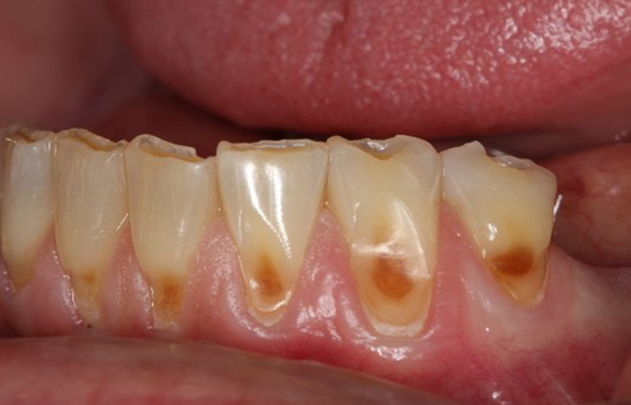

Fig 3. Facial erosion of maxillary (Fig 2) and mandibular (Fig 3) anterior teeth.

Figure 3